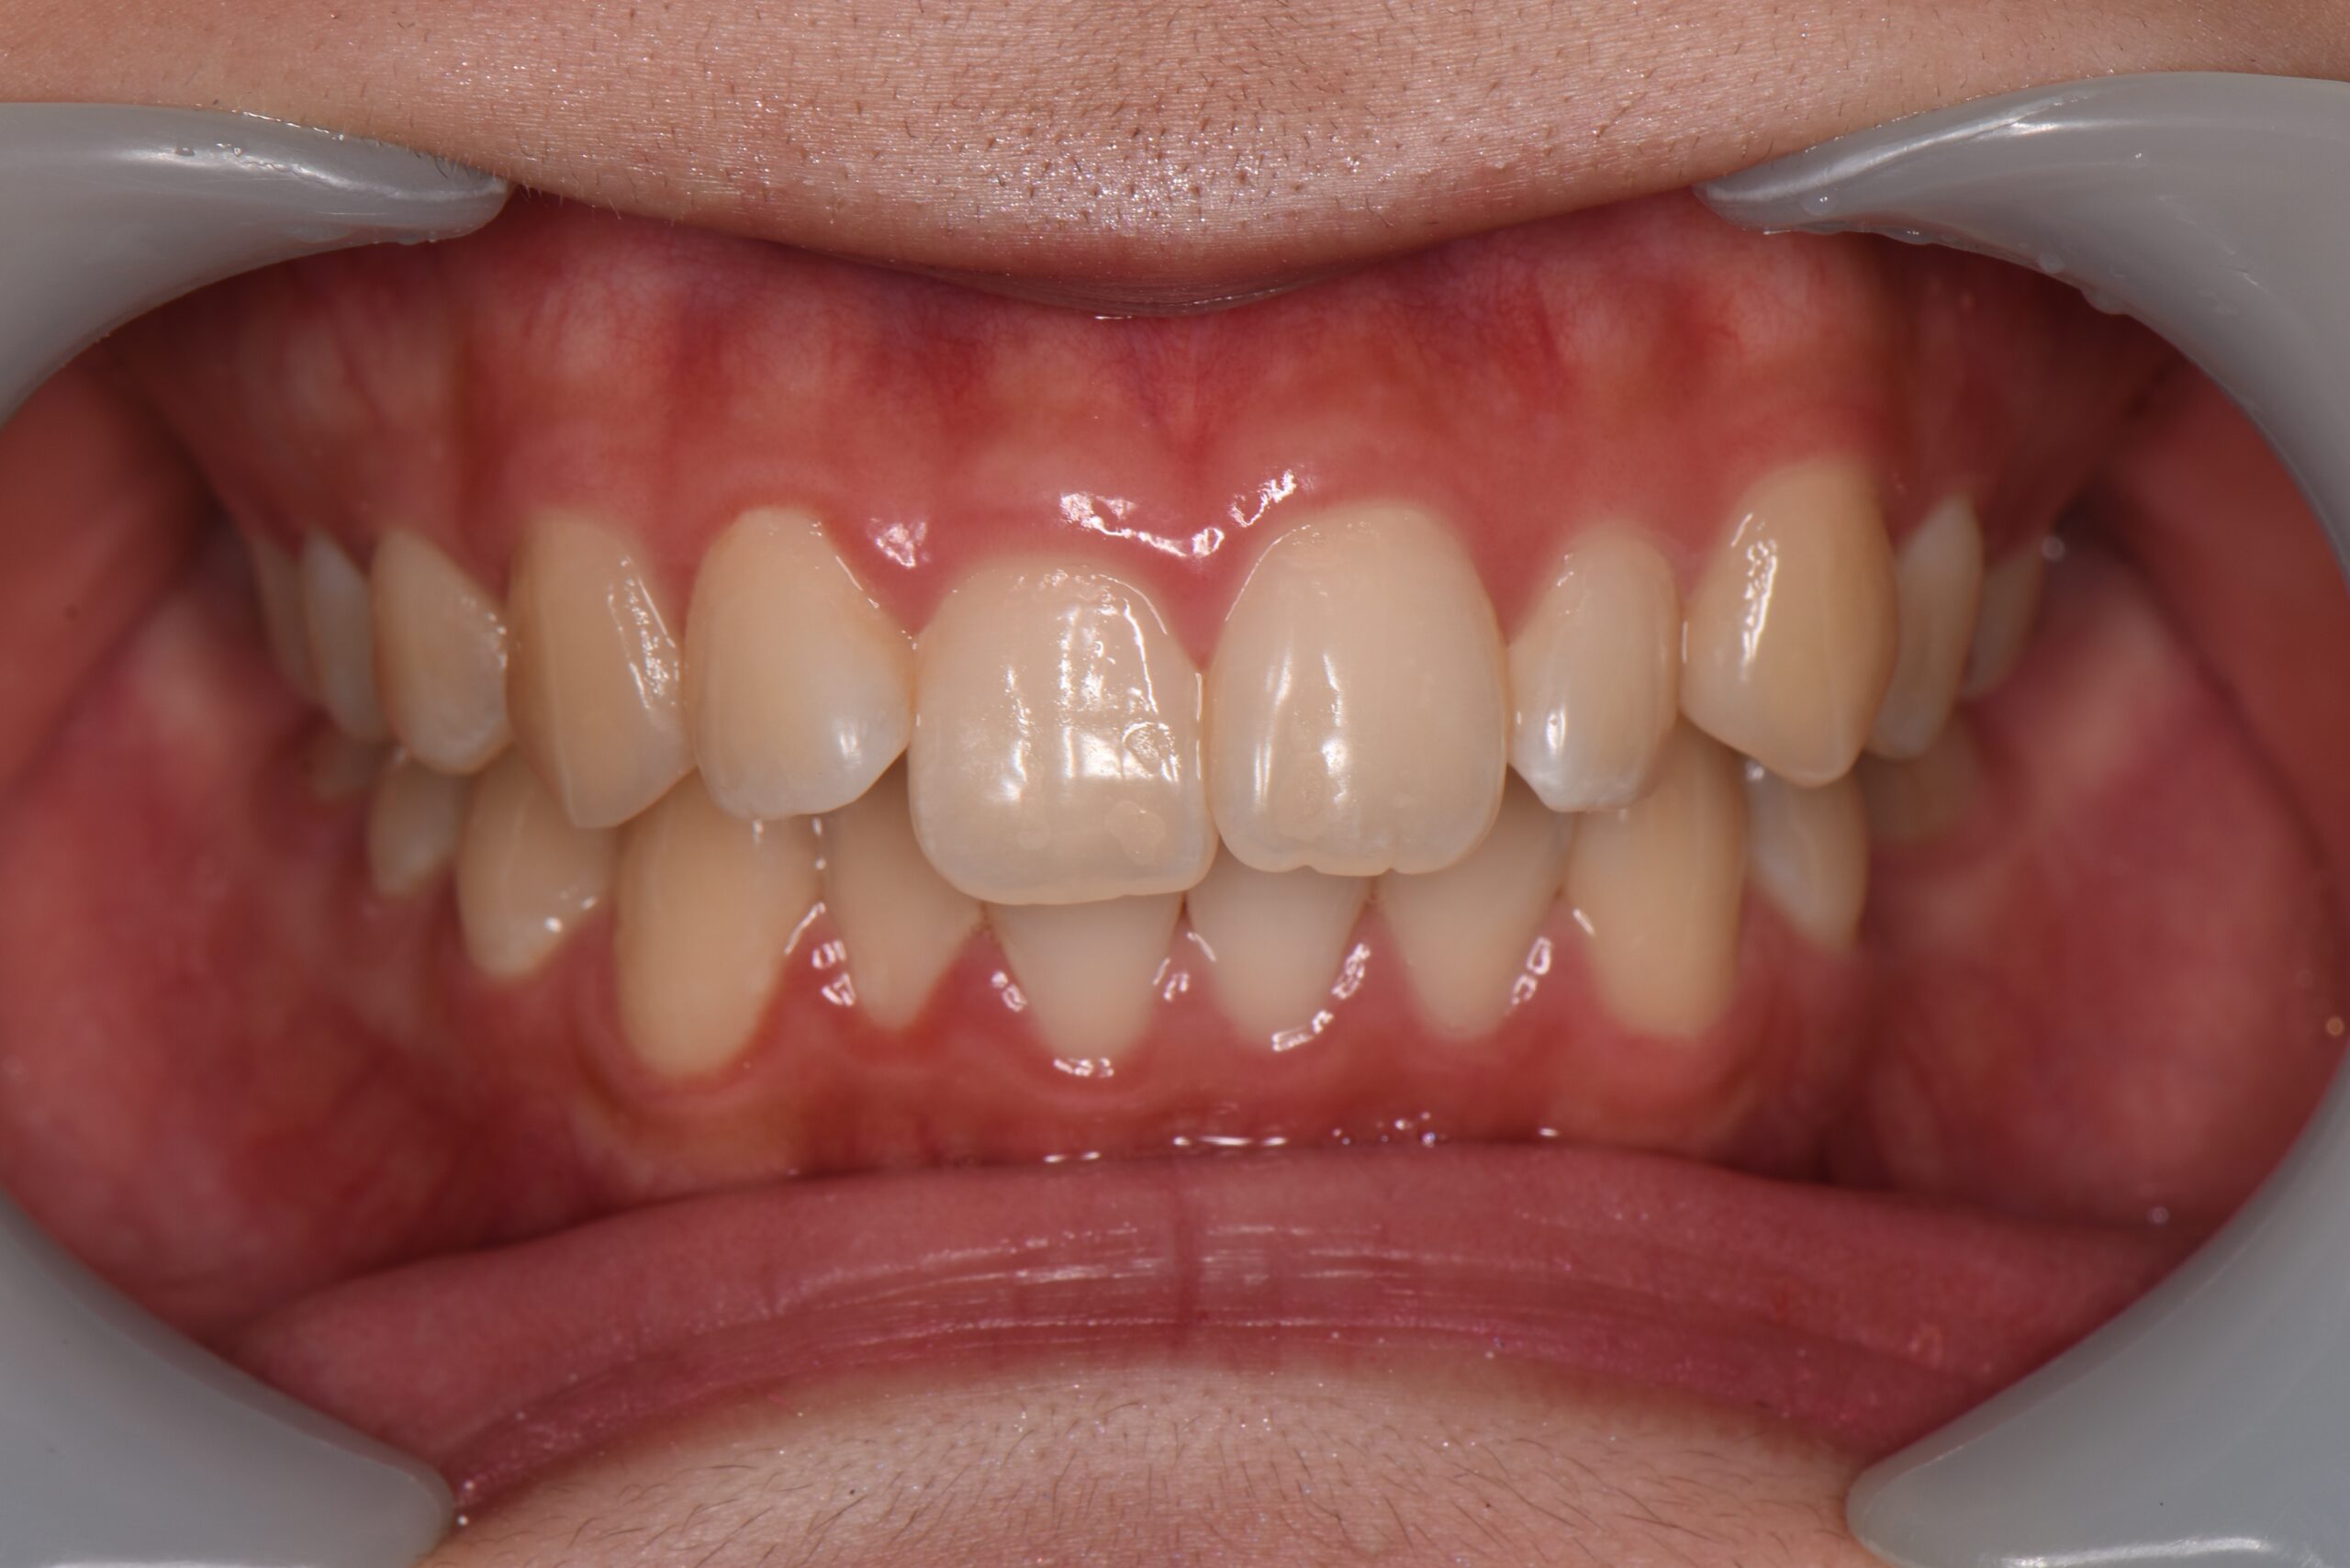

上の前歯が他の歯に比べて前に突き出ている状態です。

見た目のお悩みに限らず、口が閉じにくいためお口の中が乾燥して菌が繁殖し、むし歯や歯周病のリスクが高まります。